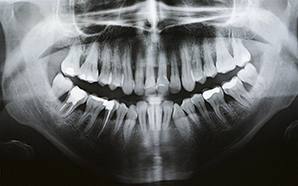

SERVICIOS